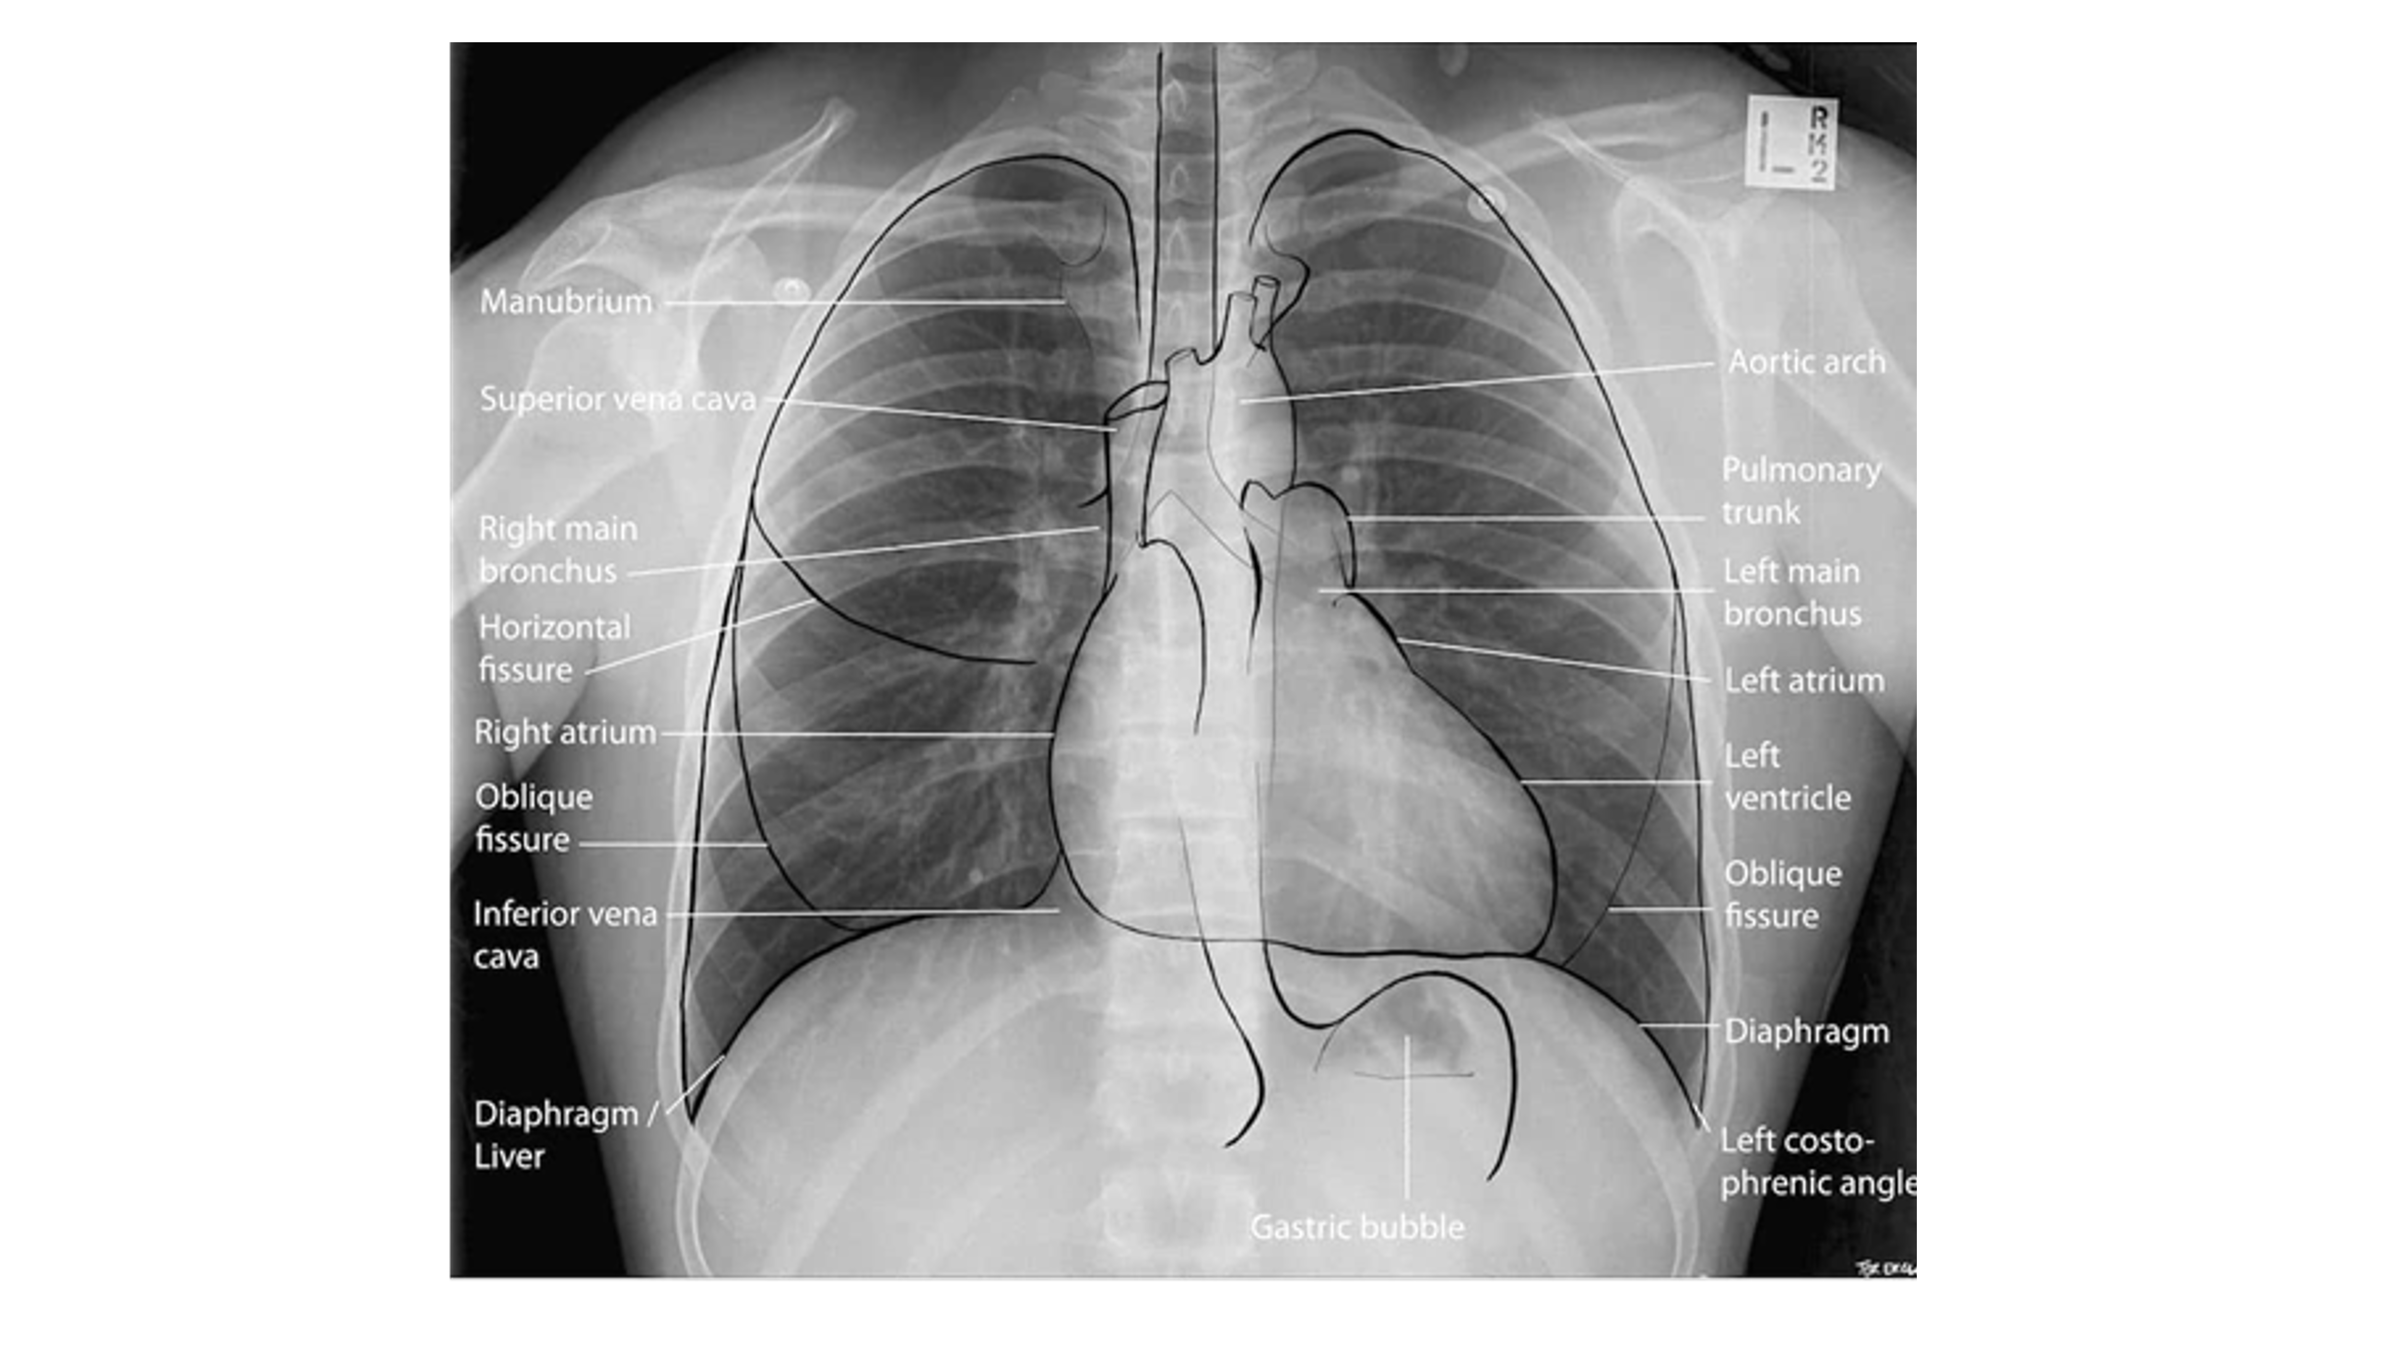

Normal CXR (PA & Lateral)

Name the mediastinal contours according to the numbers

1- superior vena cava

2- right atrium

3- inferior vena cava

4- aortic arch or knob

5- left pulmonary trunk

6- left pulmonary artery

7- left atrium

8- left ventricle

9- left cardiophrenic angle

Airway Structures on CXR

Name the structures according to number